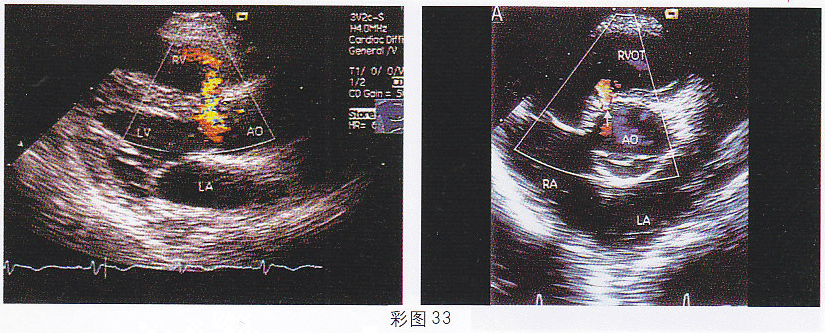

3.患儿,1岁,男,体检发现胸骨左缘全收缩期杂音,超声检查如图(彩图33)所示。该图所示的室间隔缺损属于哪型

正确答案:A 解题思路:室间隔膜部缺口处探及过隔血流信号。